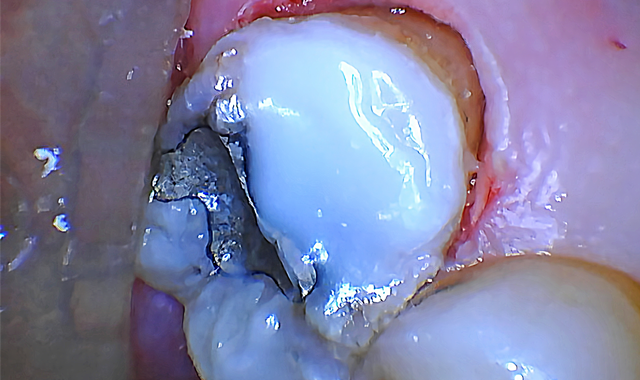

The bone was ablated until the osseous crest was 2 mm apical to restorative margins (Fig. 4). Both steps were completed with virtually no bleeding.

To finish, a piezoelectric scaler was used to smooth the surgical site and a temporary restoration (Scotchbond™ Universal Adhesive, 3M and Beautifil Flow Plus, Shofu) was placed to prevent gingiva from growing back over the tooth structure. (Fig. 5).

Fig. 4 Fig. 5